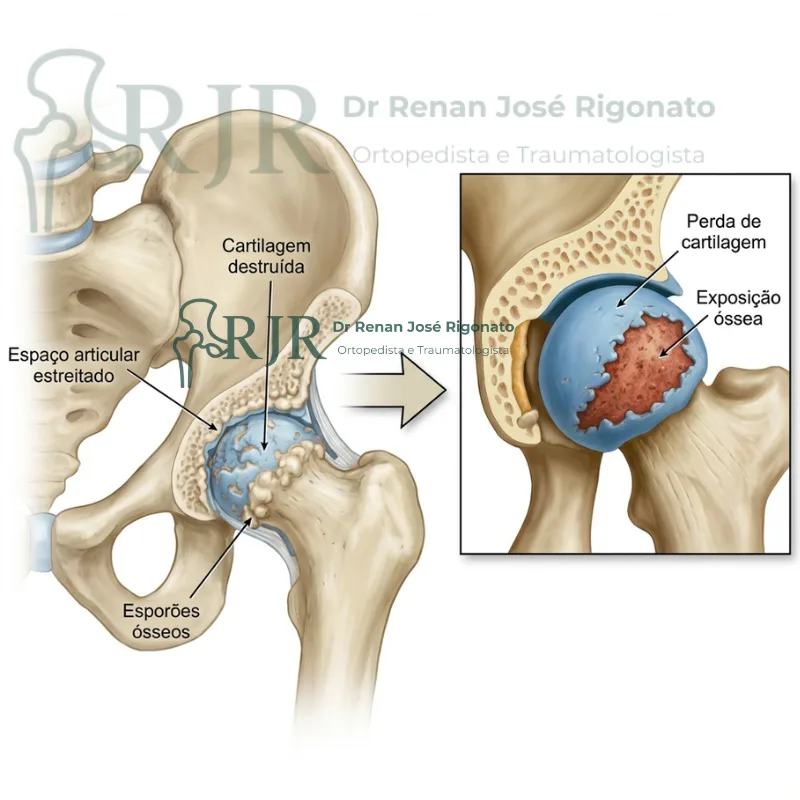

Desgaste/artrose do quadril

Principal causa de dor e limitação de movimentos. O diagnóstico precoce e tratamento personalizado ajudam a aliviar os sintomas.